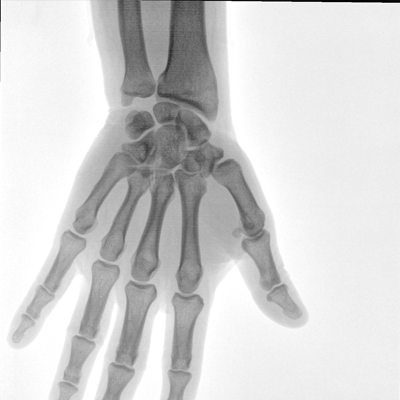

大尺寸液晶顯示器,圖像顯示清晰細(xì)膩;顯示器可大角度旋轉(zhuǎn),滿足臨床多角度觀察圖像的需要。

具備束光器預(yù)覽功能,可以在無射線狀態(tài)下,實現(xiàn)曝光范圍大小的調(diào)節(jié);大幅減少臨床反復(fù)曝光帶來的射線輻射;并自動調(diào)整圖像興趣區(qū)大小與位置,使自動模式更準(zhǔn)確。

濾線柵可插拔式設(shè)計符合行業(yè)標(biāo)準(zhǔn),用于兒科和其他劑量敏感的臨床應(yīng)用,使用簡便,保障圖像清晰的同時,可有效防護輻射危害。